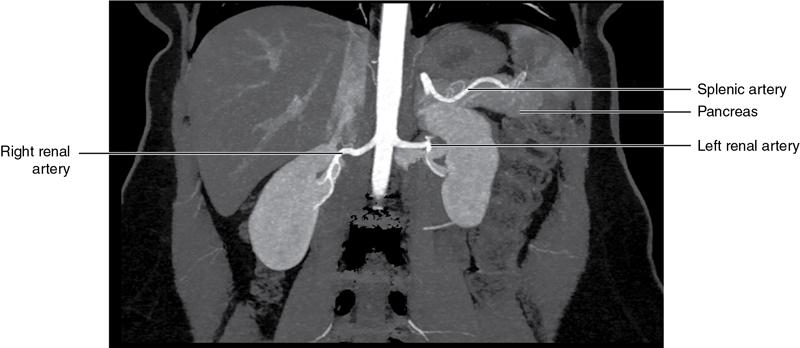

CROSS SECTIONAL ANATOMY OF ABDOMEN Satya Jha NORMAL ANATOMY OF ABDOMEN AND PELVIS Amandeep Singh The two major surfaces: The anterior and posterior layers of the coronary ligament converge on bare area (not covered by peritoneum). Its right and left margins form the right and left triangular ligaments. The right triangular ligament extends toward the diaphragm and separates right subphrenic space from right subhepatic space. The left triangular ligament gives tracts extending to the diaphragm and falciform ligament and does not compartmentalize the left subphrenic space. Ligamentum teres or the obliterated umblical vein is contained in falciform ligament which attaches the liver to anterior abdominal wall. The main portal vein, the proper hepatic artery and the common bile duct are contained within investing peritoneal folds of hepatoduodenal ligament at the porta hepatis (Fig. 7.2.2.1). Liver is divided into eight segments which are functionally independent and have their own vascular supply and biliary drainage. Arterial circulation: The branches of the hepatic artery accompanying the portal veins. Hepatic venous system: The right, middle, and left hepatic veins draining into IVC (Figs. 7.2.2.2 and 7.2.2.3). The gallbladder is a blind pear-shaped muscular membranous sac which is an embryologic derivative of the foregut, is a pouch lying along the undersurface of the liver. The gallbladder fossa is located in the plane of the interlobar fissure, which lies between the right and left hepatic lobes. Its major function is to store and concentrate bile which is produced by the liver. It measures approximately 4 cm in diameter when it is normally distended. Gallbladder is a smaller tubular structure in contracted state. The normal gallbladder wall thickness ranges from 1 to 3 mm. The gallbladder is divided into the fundus, body and neck. Infundibulum is present in the region of neck of the gallbladder, which is called the Hartmann pouch, where gallstones are usually impacted. Intrahepatic biliary radicles (IHBRs) scattered throughout the liver get confluent towards the hilum. They unite to form the right and left main hepatic ducts which further unite to form common hepatic duct (CHD) at the hilum. Common bile duct is formed by the union of cystic duct with common hepatic duct. The main pancreatic duct is joined with the common bile duct to form the ampulla of Vater at the major duodenal papilla (Figs. 7.2.2.4 and 7.2.2.5). Pancreas is located in anterior pararenal space of retroperitoneum anterior to perirenal (Gerota’s) fascia and posterior to parietal peritoneum. It is divided into head, uncinate process, neck, body and tail from right to left. Pancreas lies anterior to portal vein, which marks the point of transition between the body and neck. The region between head of pancreas and second and third parts of duodenum is known as the pancreatic groove. In postnephrectomy cases or with agenesis of kidney or ectopic kidney, pancreas moves posteriorly to partially fill in the empty renal fossa; its soft tissue density should not be mistaken for recurrent tumour. It is located in the pancreatic groove and is bounded superiorly by the duodenal bulb, laterally by second portion of duodenum, inferiorly by third portion of duodenum, medially by superior mesenteric vein and anterior to inferior vena cava. It is a wedge or wedge shaped lying posterior to superior mesenteric artery and vein. It is an imaginary junction between the head and body and lies directly over the junction of the splenic vein and superior mesenteric vein. It is located posterior to the lesser sac and anterior to the aorta, left adrenal gland, left kidney, and renal vessels and runs obliquely upward to the left of the superior mesenteric vessels. It is situated median to the colonic flexure and anterior to the left kidney. It is located in close proximity to the splenic hilum without a notable relation with the body of pancreas. It is seen anterior to the left kidney and median to the colonic flexure. The distal part of the tail passes between the peritoneal layers of the splenorenal ligament (Fig. 7.2.2.6 and 7.2.2.7).